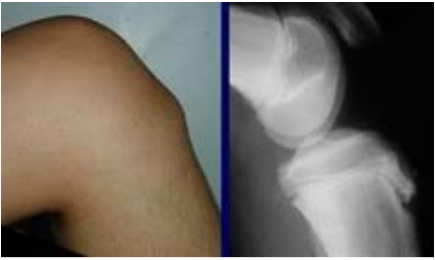

Hình minh họa: viêm điểm bám gân lồi củ trước xương chày. Nguồn: internet